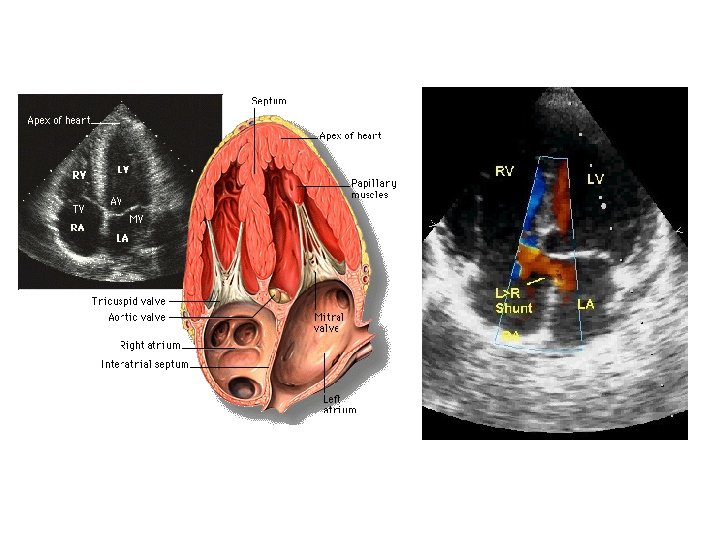

Clinical considerations